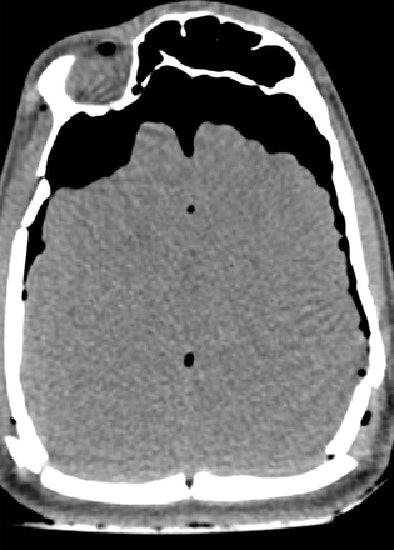

| Features of a gunshot wound to the head at virtual autopsy. Top and below, transverse CT images of a lethal gunshot wound to the head show multiple calvarial fractures, posterior settling of the brain, and pneumocephalus. Metallic fragments and foci of gas are present in the left cerebellum (below). A distinct linear bullet track is not present. Bottom, 3D volume-rendered image of the skull shows the comminuted fracture of the posterior skull. Republished with permission of the Radiological Society of North America from Radiology (August 2006, Vol. 240:2, pp. 522-528); published online before print as 10.1148/radiol.2402050972. |

Of 78 wound tracks, 10 (13%) were not seen at MDCT, the group reported. The missed tracks included six upper extremity wounds and four thigh wounds. In two cases, however, findings missed at autopsy (fracture of the cervical spine, bullet fragments in the posterior area of the neck) were identified at MDCT.

"We have shown that virtual autopsy with multidetector CT can aid prediction of lethal wound and fragment localization in victims with high-velocity gunshot wounds," the authors concluded. "Single gunshot wound tracks are well-defined. The major limitation occurs in classifying and identifying intersecting and co-mingling tracks."